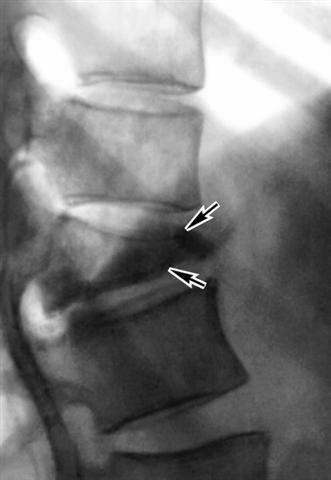

Рис. 3б). Рентгенограмма позвоночника при туберкулезном спондилите (боковая проекция): обширная деструкция тела XII грудного позвонка (указан стрелками) с его клиновидной деформацией и скобкообразными тенями оссификации в переднебоковых отделах.